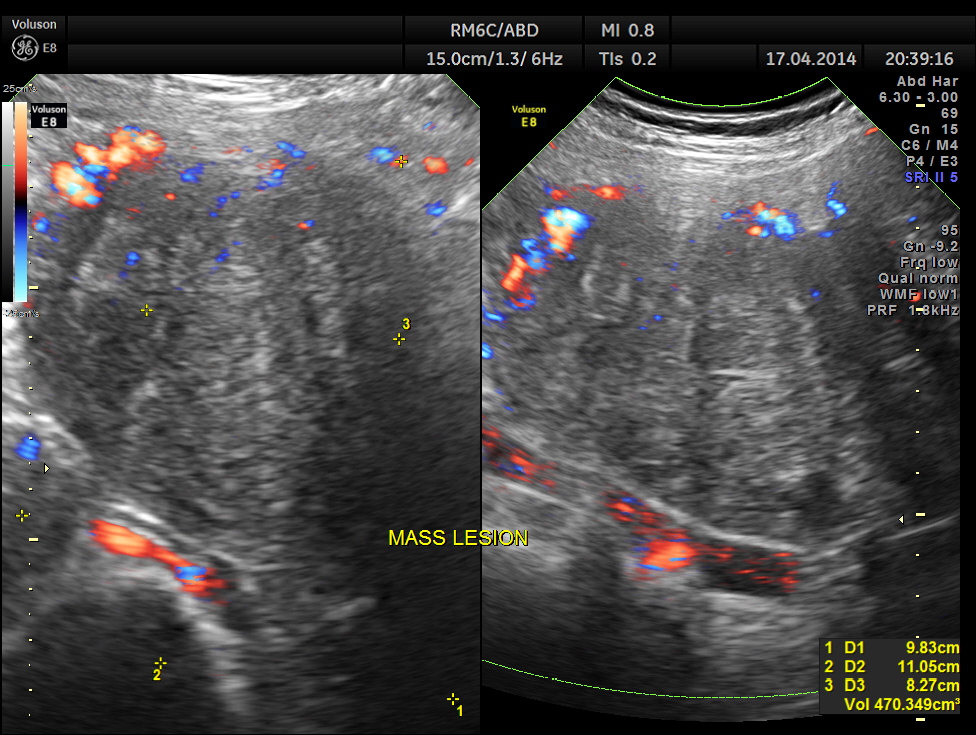

Thw two masses seen out of the uterus and mainly in the right upper quadrant are shown below.

The ultrasound gave us a few inconclusive findings . Uterus was massively enlarged ; a large fibroid was seen ; adenomyosis was seen ; endometrium was thickened ; two large mass lesions were seen in the right upper quadrant and right lumbar region . But it was difficult to ascertain the origin of these extra uterine masses .

Enlarged uterus with leiomyoma with mucinous and cystic degeneration and adenomyosis and two large sub serous fibroids arising from the fundal and right lateral aspect undergoing hyalinisation.

Reported as subserous and pedunculated . Looking at the pictures it appears as pedunculated